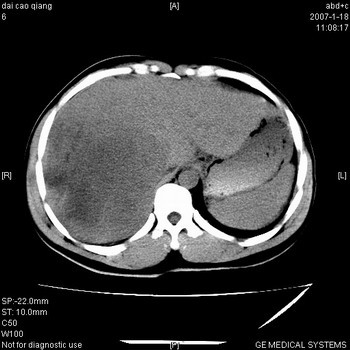

符合巨块型肝癌表现:

1、平扫低密度,增强后表现为快进快出。

3、并可见门静脉右支癌栓形成

4、可见假包膜

肝右叶巨大不均匀低密度肿块,前缘有假包膜,增强明显的呈快进快出表现,门脉右支有癌栓,病人虽然年轻但还是首先考虑肝右叶巨块形肝癌,病人血象高只能说有合并感染。不支持肝脓肿。